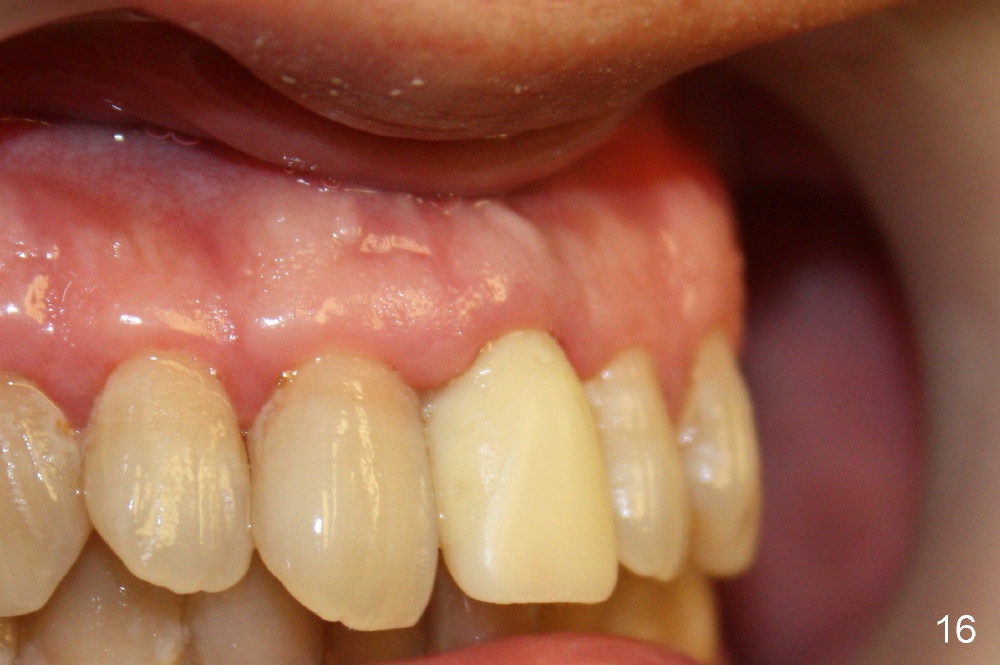

Bone expansion allows the implant (Fig.9 I) to have primary stability (insertion torque between 50 and 60 Ncm), since the cortex of the incisive canal is apparently intact. Allograft is placed in the labial gap (Fig.10, 11 *) following installation of the abutment (A). Finally an immediate provisional (Fig.10,12 P) is cemented. Fig.13,14 are taken 8 days postop. The patient returns 3 months postop (Fig.15,16). Osteointegration appears to have occurred (Fig.15 arrowheads) and is more obvious 9 months postop (Fig.17).

The permanent crown is temporarily cemented because of misshade and undercountour at the cervix (Fig.18).